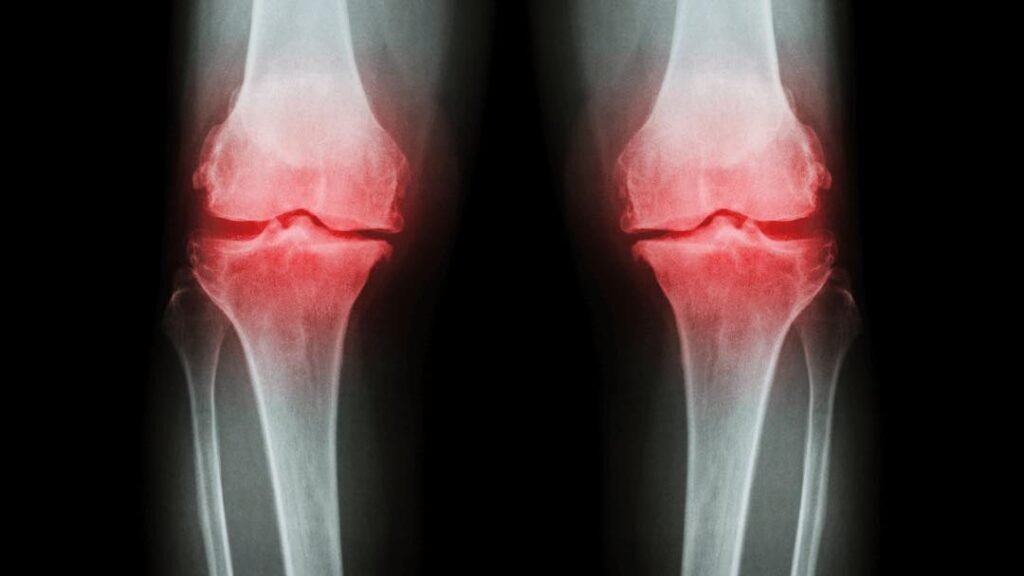

🧩 So Where Does Knee Osteoarthritis Really Come From?

Knee osteoarthritis does not arise from a single cause.

It is a whole-joint disease.

✔️ Cartilage thinning and breakdown

✔️ Poor load distribution → narrowing joint space

✔️ Chronic low-grade inflammation inside the joint